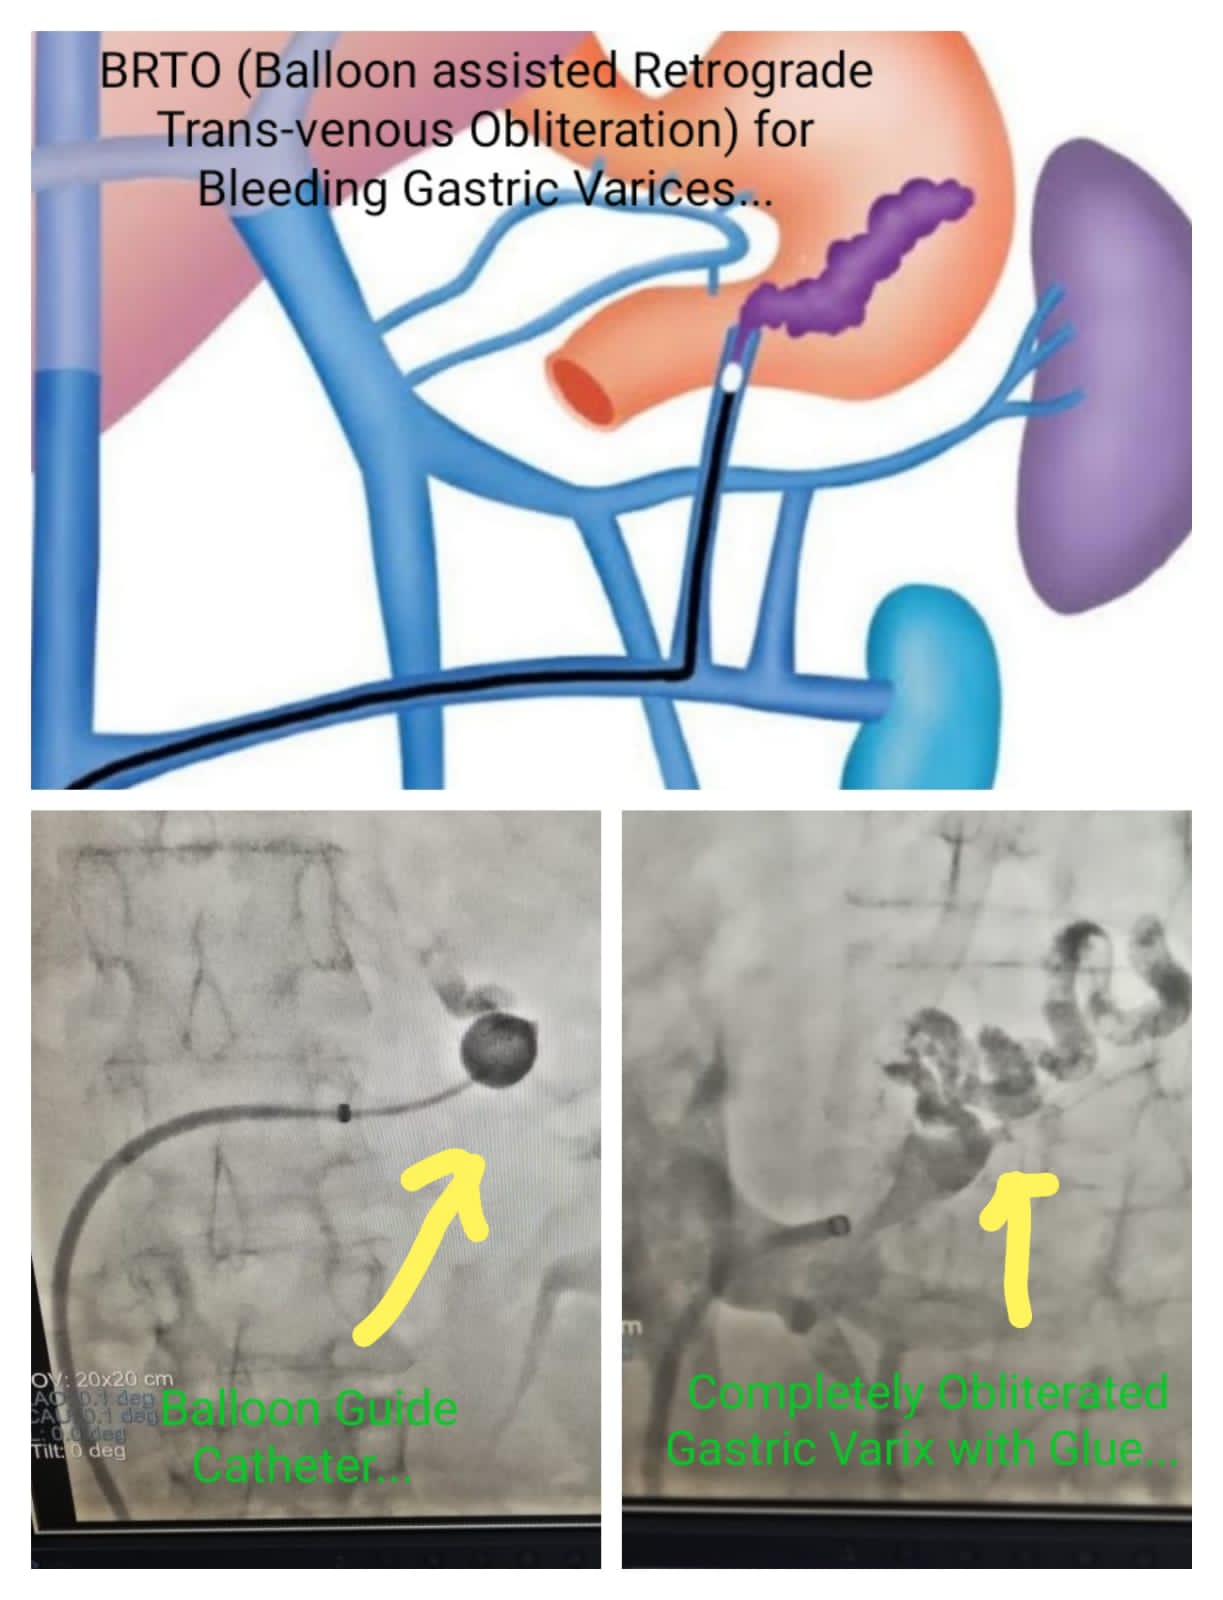

Balloon assisted retrograde Trans- Venous Obliteration for Bleeding Gastric Varices